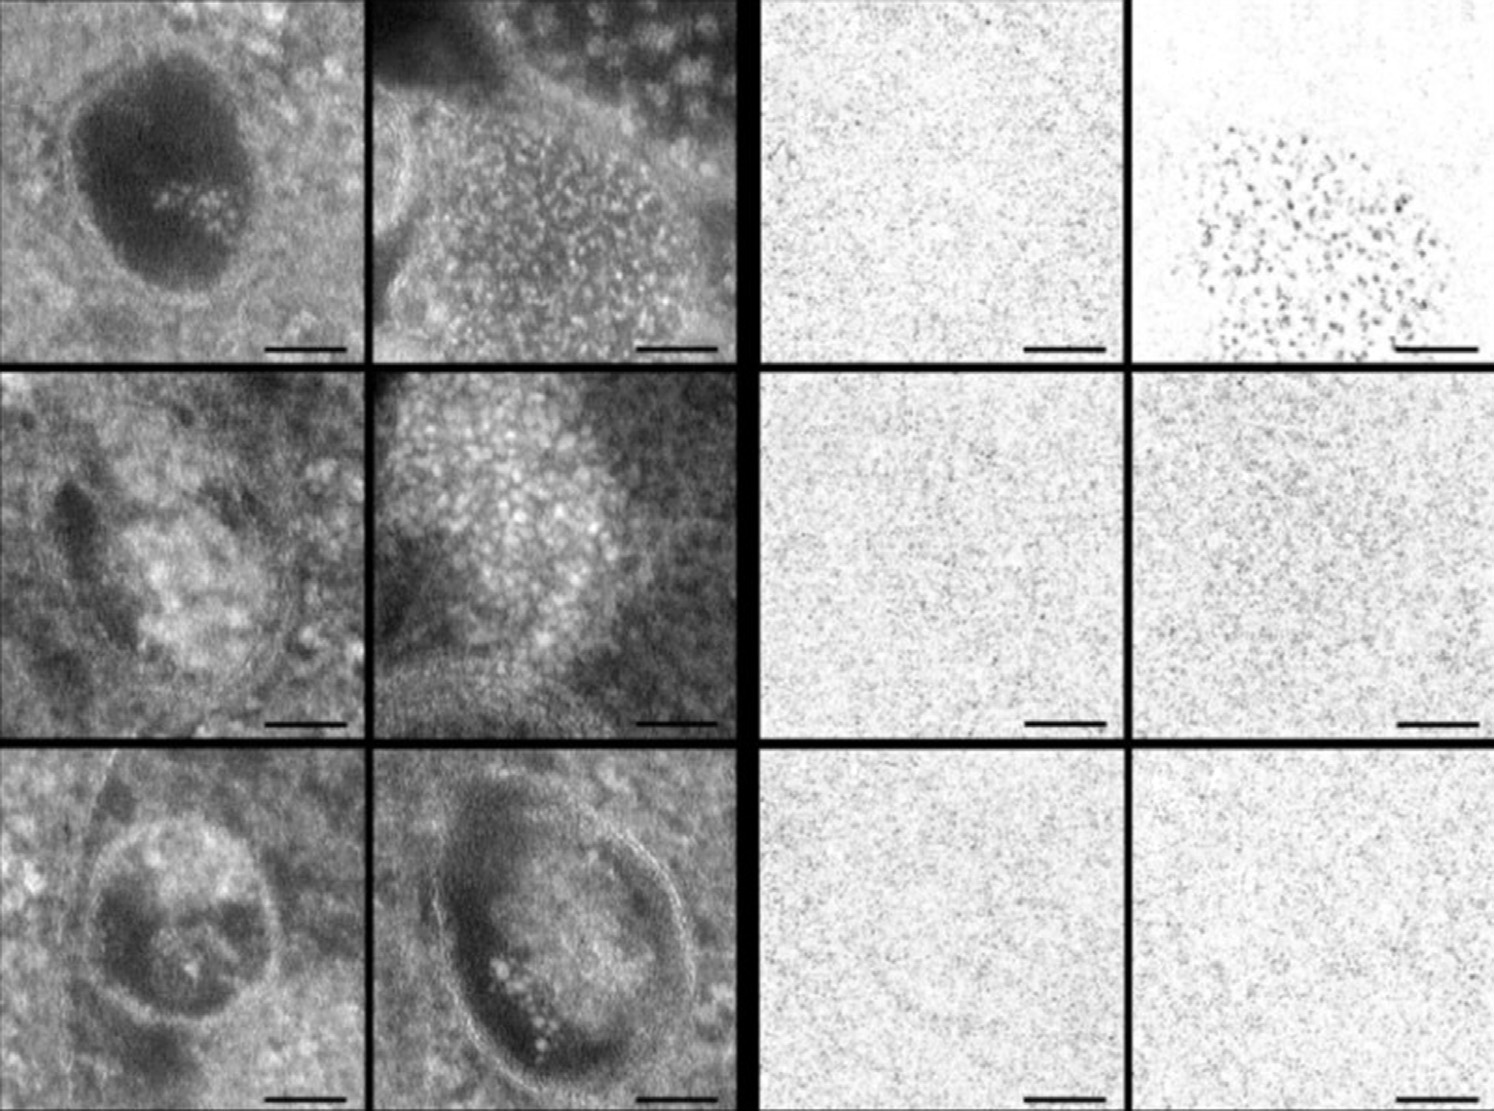

在一项研究中,观察到量子点位于内体和溶酶体囊泡中(图8.8)。这种运输方式模拟了载药纳米颗粒所经过的途径。量子点结合透射电子显微镜技术和共聚焦显微镜技术正在被探索作为研究纳米结构细胞内运输的有力工具。除了内体和溶酶体区室外,量子点还可靶向其他细胞器,如线粒体和细胞核[70]。23个氨基酸的细胞核定位信号和28个氨基酸的线粒体定位信号的共轭可分别导致量子点在细胞核和线粒体中的定位。在细胞摄取开始后30分钟内,量子点即定位于相应的区室[70]。将信号肽与量子点共轭可揭示特定细胞器摄取过程的相关机制和途径。该过程使我们能够开发可特异性靶向特定细胞器的载药纳米结构。肽偶联量子点还使我们能够确定纳米结构在不同靶向细胞器中的定位动力学。